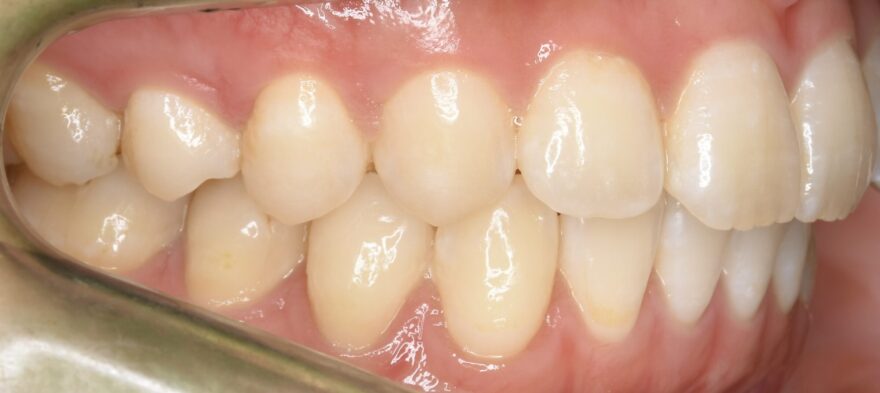

治療後の口腔内写真

約2年の治療期間で、ここまで美しい歯並びになりました。

前歯も綺麗に並びました。

インプラントの上部構造は仮歯からセラミック歯へと交換しています。

下顎の前歯にはワイヤーによる保定装置を装着しました。